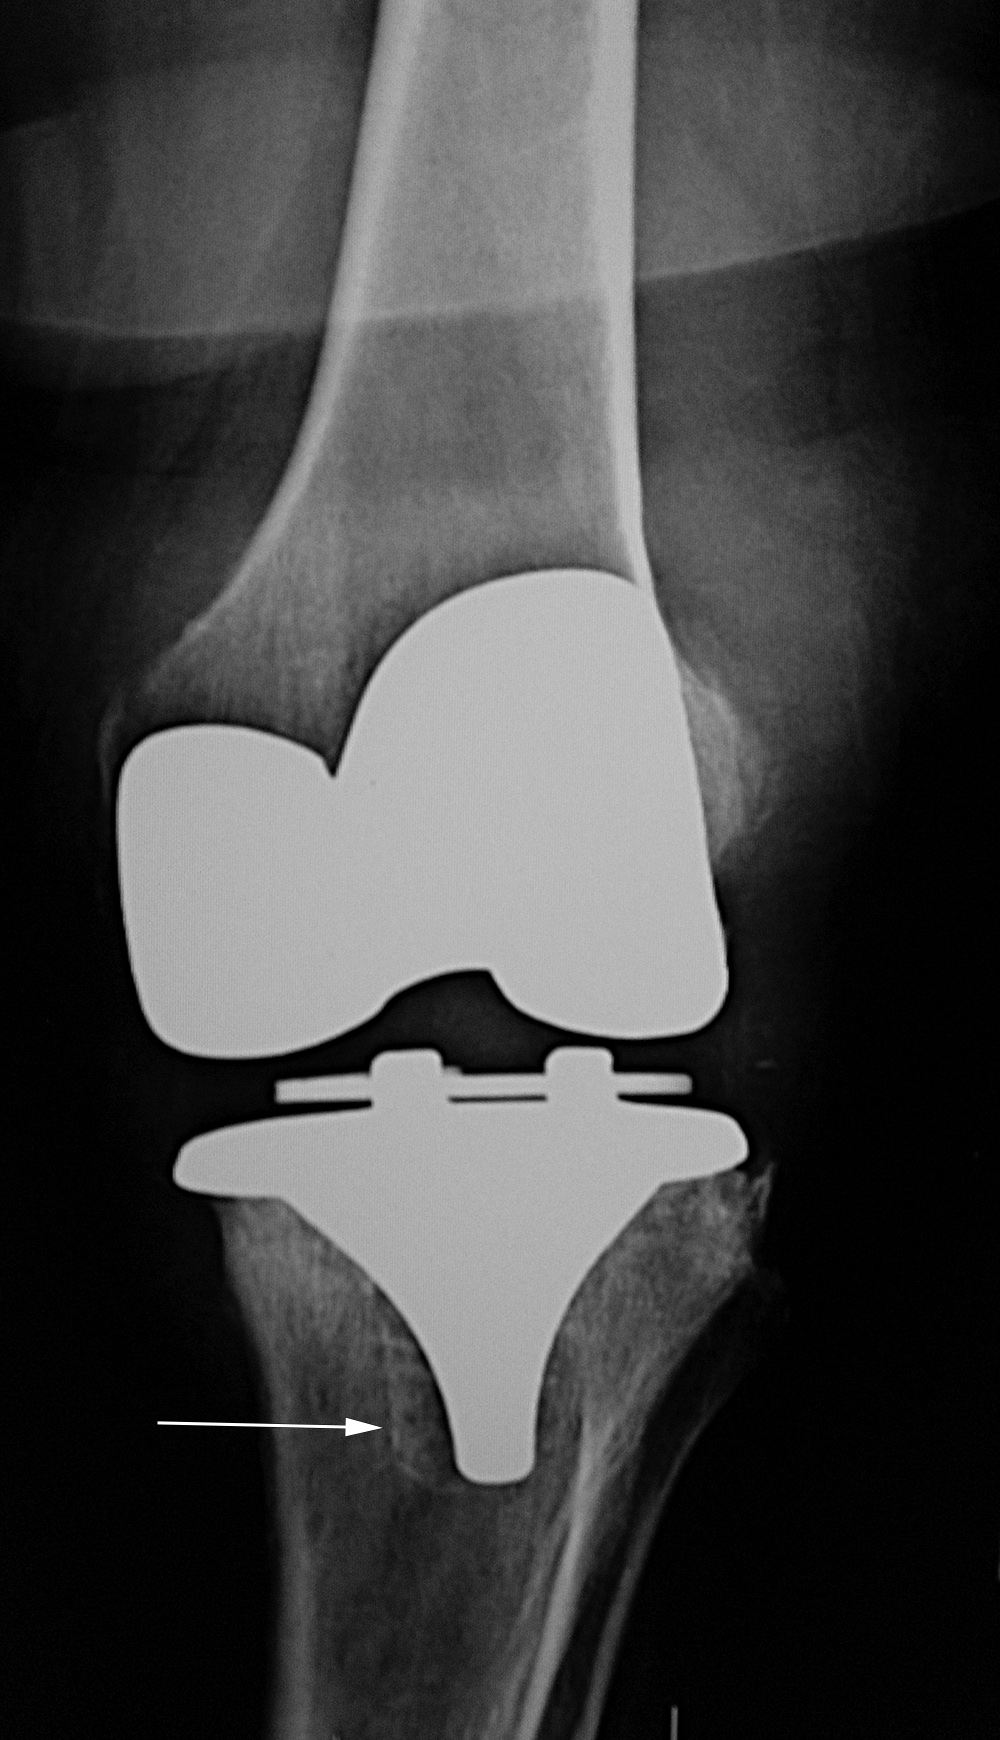

| Aseptic loosening of bilateral total knee arthroplasties |

| 65 year-old woman with bilateral cruciate-retaining total knee arthroplasties (TKAs) placed in early 2009. In November 2015 routine follow-up showed bilateral aseptic loosening in both tibial components with wide periprosthetic lucencies (arrows) and varus deformity on the left. From left to right, respectively, AP radiograph of the left knee in the postoperative period, AP radiograph of the left knee 6.5 years later, lateral radiograph of the left knee in the postoperative period, and lateral radiograph of the left knee 6.5 years later. Images courtesy Laura H Lee, MD. |

| Aseptic loosening of bilateral total knee arthroplasties continued |

| 65 year-old woman with bilateral cruciate-retaining total knee arthroplasties (TKAs) placed in early 2009. In November 2015 routine follow-up showed bilateral aseptic loosening in both tibial components with wide periprosthetic lucencies (arrows) and varus deformity on the left. From left to right, respectively, AP radiograph of the right knee in the immediate postoperative period, AP radiograph of the right knee 6.5 years later, and standing frontal view of the knees 6.5 years after surgery. Images courtesy Laura H Lee, MD. |